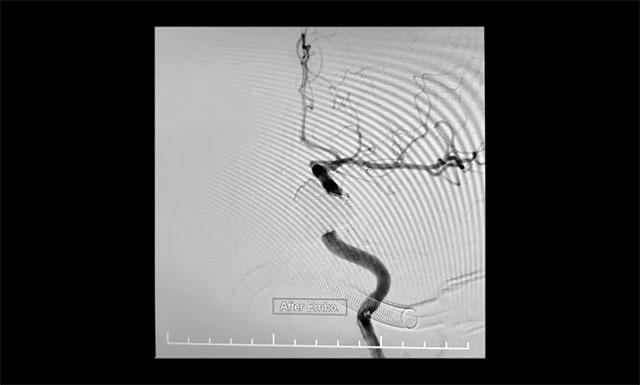

“鋼筋混凝土技術(shù)”操作時(shí)需十分謹(jǐn)慎,若注膠不足會(huì)導(dǎo)致瘺口封閉不全癥狀不緩解,而注膠不慎又會(huì)導(dǎo)致膠溢入頸內(nèi)動(dòng)脈,造成頸動(dòng)脈堵塞致大面積腦梗塞的災(zāi)難性后果。術(shù)中,張琪博士在李喆醫(yī)生、周林華醫(yī)生協(xié)助下先將海綿竇內(nèi)小心填入13枚大直徑彈簧圈作為“鋼筋骨架”,然后準(zhǔn)確地將球囊置于瘺口處的頸內(nèi)動(dòng)脈內(nèi),緩慢充盈球囊將瘺口暫時(shí)與頸內(nèi)動(dòng)脈隔離,然后小心翼翼地向瘺口內(nèi)注入onyx膠封堵,并仔細(xì)觀察膠的反流和擴(kuò)散情況。該方法每次球囊阻斷頸內(nèi)動(dòng)脈的時(shí)間不能超過(guò)6分鐘,否則將可能導(dǎo)致腦缺血。“1分鐘、2分鐘、3分鐘……”最終,經(jīng)過(guò)幾個(gè)循環(huán)的封堵,瘺口被栓塞得嚴(yán)嚴(yán)實(shí)實(shí),在確認(rèn)瘺口及主要異常回流途徑完全閉塞后,及時(shí)終止手術(shù),取得了較好的臨床效果,術(shù)中造影證實(shí)瘺口均完全閉塞。

▲ 術(shù)中造影證實(shí)瘺口均完全閉塞